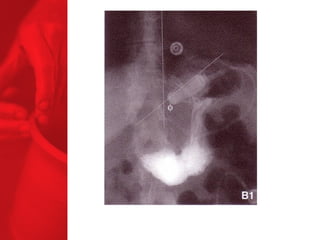

GASTRIC BYPASS Lesprocédures de malabsorption et restrictives > 56% de perte de poids excédentaire après quatre ans* > diminue le diabète de type 2 chez plus de 83 % des patients* *Christou NV, Sampalis JS, Liberman M, et al. Surgery Decreases Long-Term Mortality, Morbidity, and Health Care Use in Morbidly Obese Patients. Annals of Surgery 2004;240(3):416-424. ** Buchwald H, Avidor Y, Braunwald E, et al. Bariatric Surgery—A Systematic Review of the Literature and Meta-analysis. Journal of the American Medical Association 2004 Oct 13;292(14).

Echecs Malgré unebonne technique du CCGL, des échecs surviennent chez 15 à 20 % des patients. Les causes de reprise pondérale sont la dilatation de la poche gastrique, la dilatation de l'anastomose gastrojéjunale, l'hypertrophie des villosités du jéjunum proximal et la prise d'une alimentation avec des liquides à haute teneur en calories. Ainsi, pour les « superobèses » pathologiques (IMC > 50 kg/m2), l'intervention de référence pourrait devenir la diversion biliopancréatique.

COMMENT FONCTIONNE LECOURT-CIRCUIT GASTRIQUE ? Facteurs chirurgicaux Restriction du volume des repas Certaine malabsorption Syndrome de chasse Réduction de l'appétit Facteurs pour les patients Apport en calories Dépense en calories BILAN ENERGETIQUE = apport alimentaire dépense en énergie